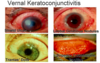

How does Vernal keratoconjuctivitis (VKC) present and how is it managed?

- Typical patient is atopic boy living in a warm, dry climate with severe bilateral symptoms in spring (itchy eyes, foreign body sensation, pho- tophobia) and giant cobble-stone papillae under the upper eye lid

- Lid skin is spared, unlike AKC

- Rx: Olopatadine drops. If uncontrolled or if corneal disease devel-ops, steroid drops are needed (eg 1% prednisolone acetate/2h; taper rapidly).

Corneal involvement needs careful eye clinic review and coverage with steroids, antibiotic drops, and lid hygiene to limit staphylococcal colonisation